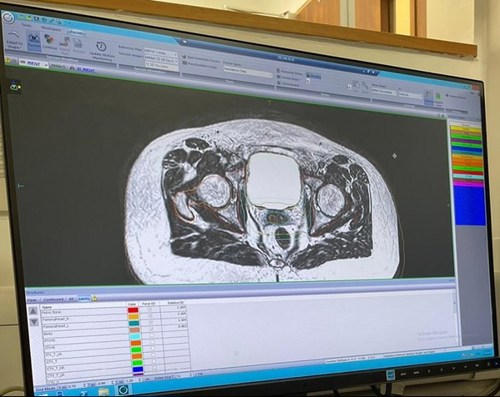

Last month, we rolled out our adapt to shape (ATS) lite workflow for prostate patients. In this workflow, the more complex ATS algorithm is utilised without the need to recontour structures. This ultimately ensures better dose conformity for organs at risk (OARs) and to the prostate.

The workflow will be further developed in the future by grouping the contours so quick adjustments can be made to account for anatomical movement. We are hoping this will increase efficiencies to treat patients allowing for a flexible but efficient planning process.